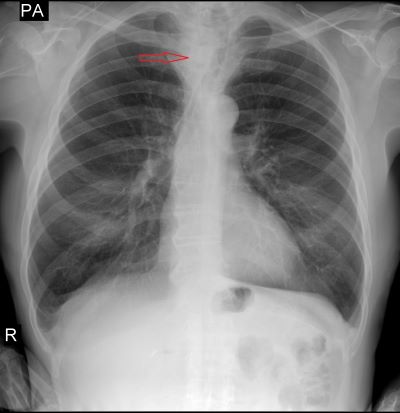

Пациенту была выполнена рентгенография органов грудной полости сначала в прямой проекции, и при подозрении на наличие дополнительной тени, была выполнена боковая проекция.

При анализе, полученных изображений была выявлена тень, которая смещала трахею кпереди и влево, размерами 35х40х44 мм. Рекомендовано дообследование в КТ-кабинете.